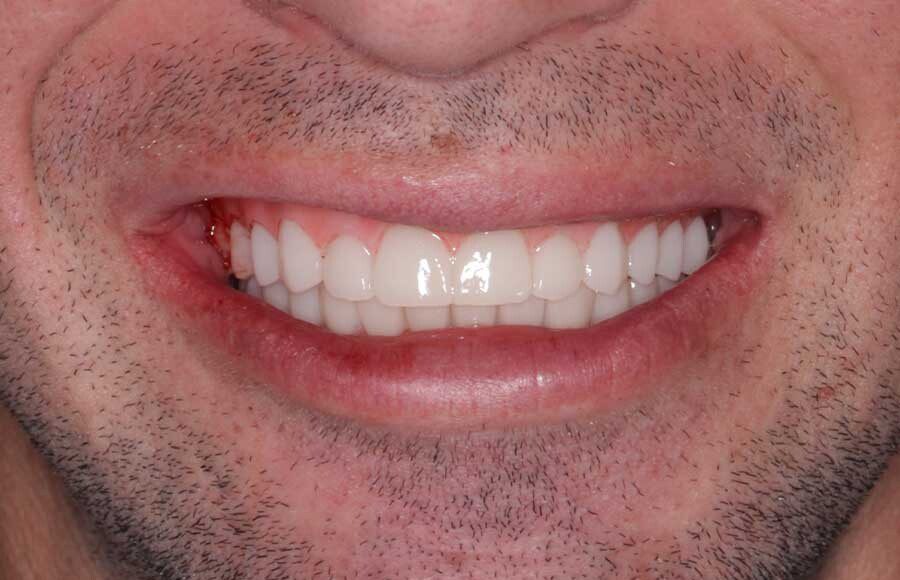

Smile GalleryImplant RestorationsImplant Dentures Post-op smiling 1 of 32 Pre-op close up smiling Pre-op lips retracted smiling Pre-op panoramic x-ray Implants in upper jaw (occlusal view) Implants in lower jaw (occlusal view) Panoramic x-ray of implants First set of try-ins – upper denture First set of try-ins – lower fixed provisional Delivered try-ins (lips retracted) Close adaptation to gums and appropriate emergence profile of lower fixed provisional Gum tissues have been molded by a convex provisional Delivered try-ins Second set of try-ins (lips retracted) Close adaptation to gums and appropriate emergence profile of second set of lower fixed provisional Delivered second try-ins Definitive restorations on casts (frontal view) Definitive restorations on cast (right side) Definitive restorations on cast (left side) Definitive upper overdenture (occlusal view) Definitive lower fixed titanium-acrylic hybrid restoration (occlusal view) Definitive lower fixed titanium-acrylic hybrid restoration (frontal view) Definitive lower fixed titanium-acrylic hybrid restoration (tissue side view) Healthy molded gum tissues on lower prior to delivery of lower fixed hybrid restoration Healthy gum tissues on upper prior to delivery of upper overdenture Definitive restorations (frontal, lips retracted) Definitive lower restoration (frontal) Definitive restorations (right side) Definitive restorations (left side) Definitive lower restoration (occlusal view) Definitive upper restoration (occlusal view) Post-op panoramic x-ray Post-op smiling